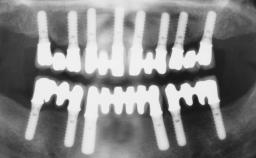

| Case Type | Short Space |

| Jaw | Maxilla |

| Area | Posterior |

| # of Teeth | 2 |

Surgical SAC classification

| Bone Volume | - |

| Anatomic Risk | - |